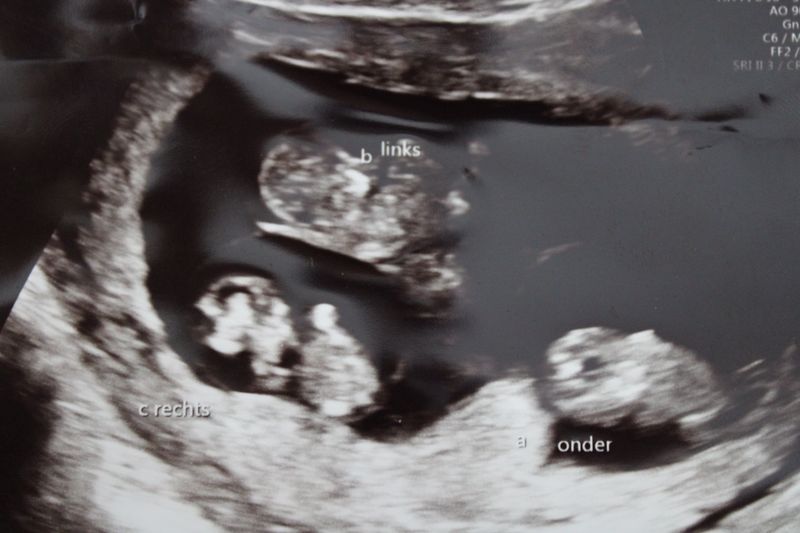

“Als het hartje maar klopt, dan is het goed. Meer is er bij een eerste echo toch niet te zien”, zei ik tegen mijn vriend. Ik fietste met ons zoontje naar de verloskundigenpraktijk. Daar aangekomen zette ik onze oudste (Musa) in de buggy die ik in de fietstas had gedaan. Ik bedacht mij dat het toch wel erg fijn was dat hij waarschijnlijk al kon lopen als de tweede zou komen. Mijn naam werd geroepen en we gingen naar binnen. Bekende gezichten van de vorige zwangerschap en we kletsten wat. “Laten we meteen maar even gaan kijken!”, riep ze enthousiast. “Nou, even kijken…”, en toen was het even stil. Heel stil. Er ging van alles door mij heen. Eerlijk gezegd wist ik zelf niet waar ik kijken moest. Ik herkende nog niet vaag een kindje in het beeld.

Het zijn er niet één of twee, maar drie

Nog steeds was het stil en ze draaide nog een aantal keer met het echo apparaat. “Zie jij dat ook?”, vroeg ze. “Uh wat moet ik zien? Is het niet goed?”. Ik geef eerlijk toe dat ik het echt niet zie. “Schrik niet, het zijn er drie!”. “Wat?!”, dacht ik. Op dat moment voelde ik alle emoties door elkaar. Ik heb gelachen, gehuild, onzin uitgekraamd en vooral heel vaak geroepen: “Hoe dan?”. Toen ik iets gekalmeerd was, zei ze zo rustig mogelijk: “Ik dacht eerst dat het er vier waren. Maar het zijn er echt drie hoor”. En daar ging ik weer, totaal in shock. Hoe past dat in mijn lijf? Zijn ze wel gezond? We moeten een andere auto en oh, ik moet mijn vriend echt bellen!

Omdat het een behoorlijk risicovolle zwangerschap was met een drieling, werden we doorgestuurd naar de gynaecoloog in het ziekenhuis. Hier konden we de volgende dag al terecht. Er werd gekeken hoe de baby’s in de buik zaten, wat ze samen deelden en wat dat betekende voor de kans van slagen. Zo begon onze rollercoaster, vorig jaar op 16 juni 2020.